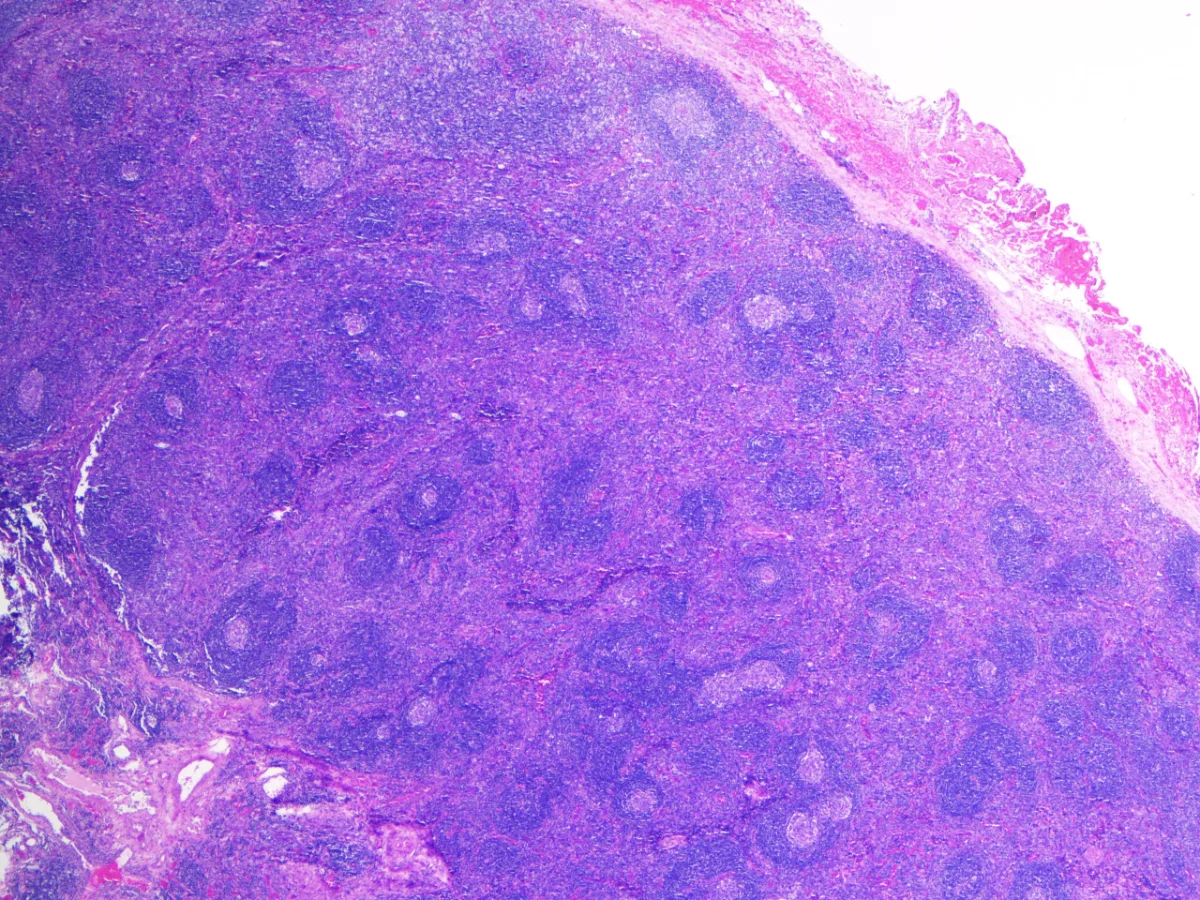

Varón de 18 años ingresado en Medicina Interna por un cuadro poliadenopático, asociado a serositis con derrame pleural y ascítico, hepatomegalia, proteinuria y anemia de 20 días de evolución. Ante la sospecha de síndrome linfoproliferativo, se realiza PET-TC (18F-FDG), que muestra adenopatías múltiples axilares izquierdas hipermetabólicas, por lo que se realiza exéresis de una de ellas.

Recibimos en nuestro servicio una adenopatía en fresco, realizamos improntas y procesamos para estudio en parafina.

Diagnóstico: Enfermedad de Castleman, variante hialino-vascular.

- La variante hialino-vascular es la más frecuente en la EC unicéntrica, y se caracteriza por una hiperplasia linfoide con centros germinales regresivos y zona del manto expandida en aspecto “en capas de cebolla”. Se acompaña de proliferación vascular en forma de vénulas con endotelio alto, y células dendríticas foliculares prominentes (PMID: 35997567).